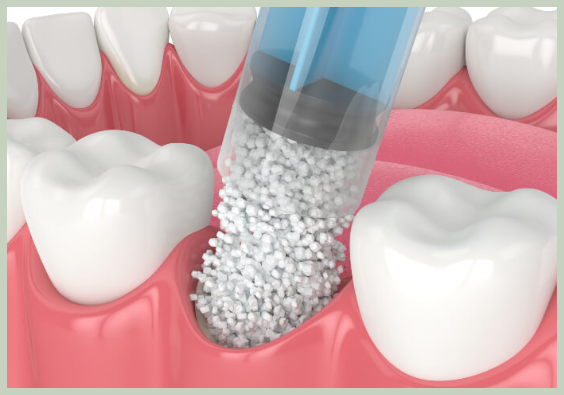

뼈이식은 부족한 잇몸 뼈를 보충하여 임플란트 식립을 가능하게 하는 시술입니다. 뼈이식 재료는 환자 본인의 뼈, 동물의 뼈, 인공 뼈 등 다양하며, 환자의 상태에 따라 적절한 재료를 선택하여 사용합니다.

뼈이식에 사용되는 재료는 크게 세 가지로 나눌 수 있습니다.

- 자가골: 환자 본인의 뼈를 이용하는 것으로, 가장 이상적인 뼈이식 재료입니다. 주로 턱 뼈, 골반 뼈, 정강이 뼈 등에서 채취하며, 면역 거부 반응 없이 안전하게 사용할 수 있다는 장점이 있습니다.

- 동종골: 다른 사람의 뼈를 이용하는 것으로, 기증받은 뼈를 가공하여 사용합니다. 자가골에 비해 뼈 형성 능력은 떨어지지만, 안전성이 높고 구하기 쉽다는 장점이 있습니다.

- 이종골: 동물의 뼈를 이용하는 것으로, 소 뼈 또는 돼지 뼈를 가공하여 사용합니다. 가격이 저렴하고 구하기 쉽지만, 면역 거부 반응 및 감염 위험이 있을 수 있습니다.

- 합성골: 인공적으로 만든 뼈 재료로, 칼슘 화합물 등을 이용하여 제작합니다. 면역 거부 반응 및 감염 위험이 적고 다양한 형태로 제작 가능하다는 장점이 있습니다.

- 절개: 잇몸을 절개하여 뼈이식을 할 부위를 노출시킵니다.

- 뼈이식 재료 삽입: 선택된 뼈이식 재료를 부족한 잇몸 뼈 부위에 삽입합니다.